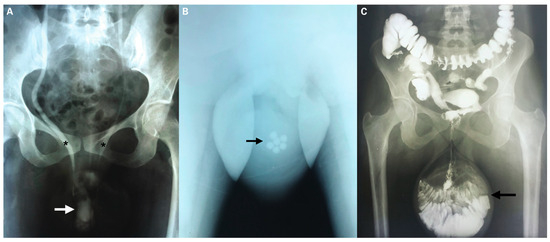

Chronic Pelvic Organ Prolapse and Bladder Calculi in an Adolescent